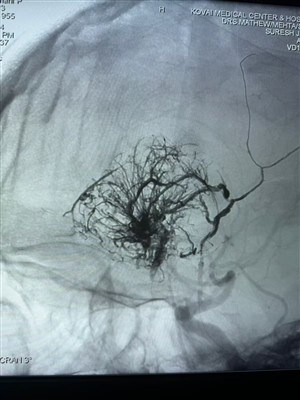

Første tilfelle av hypervaskulær svulst rapportert i IndiaGlad for å dele denne første hypervaskulære svulstsaken utført i India. Den ble behandlet med Lava Liquid Embolic System fra NeuroSafe Medical Co., Ltd. Takket være Dr. Mathew Cherian. Han var bane...